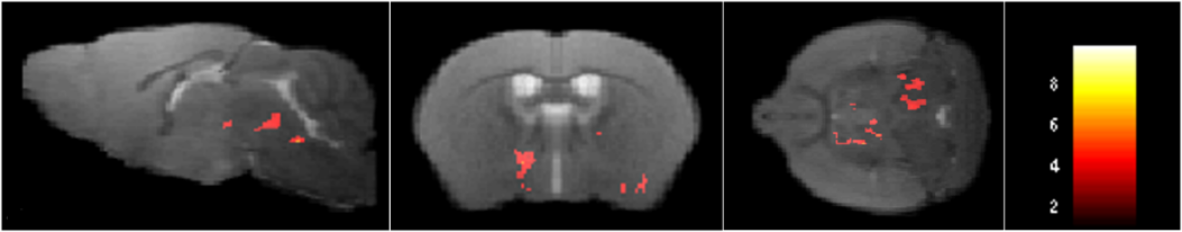

Fig. 3

Statistical analysis of ALFF activity in BOLD signals in the AD + NS group versus the AD + SSO group. The voxel-level height threshold was P < 0.005 (uncorrected). The cluster range threshold was 20 voxels. Detailed statistical information for these regions is provided in Table 2.